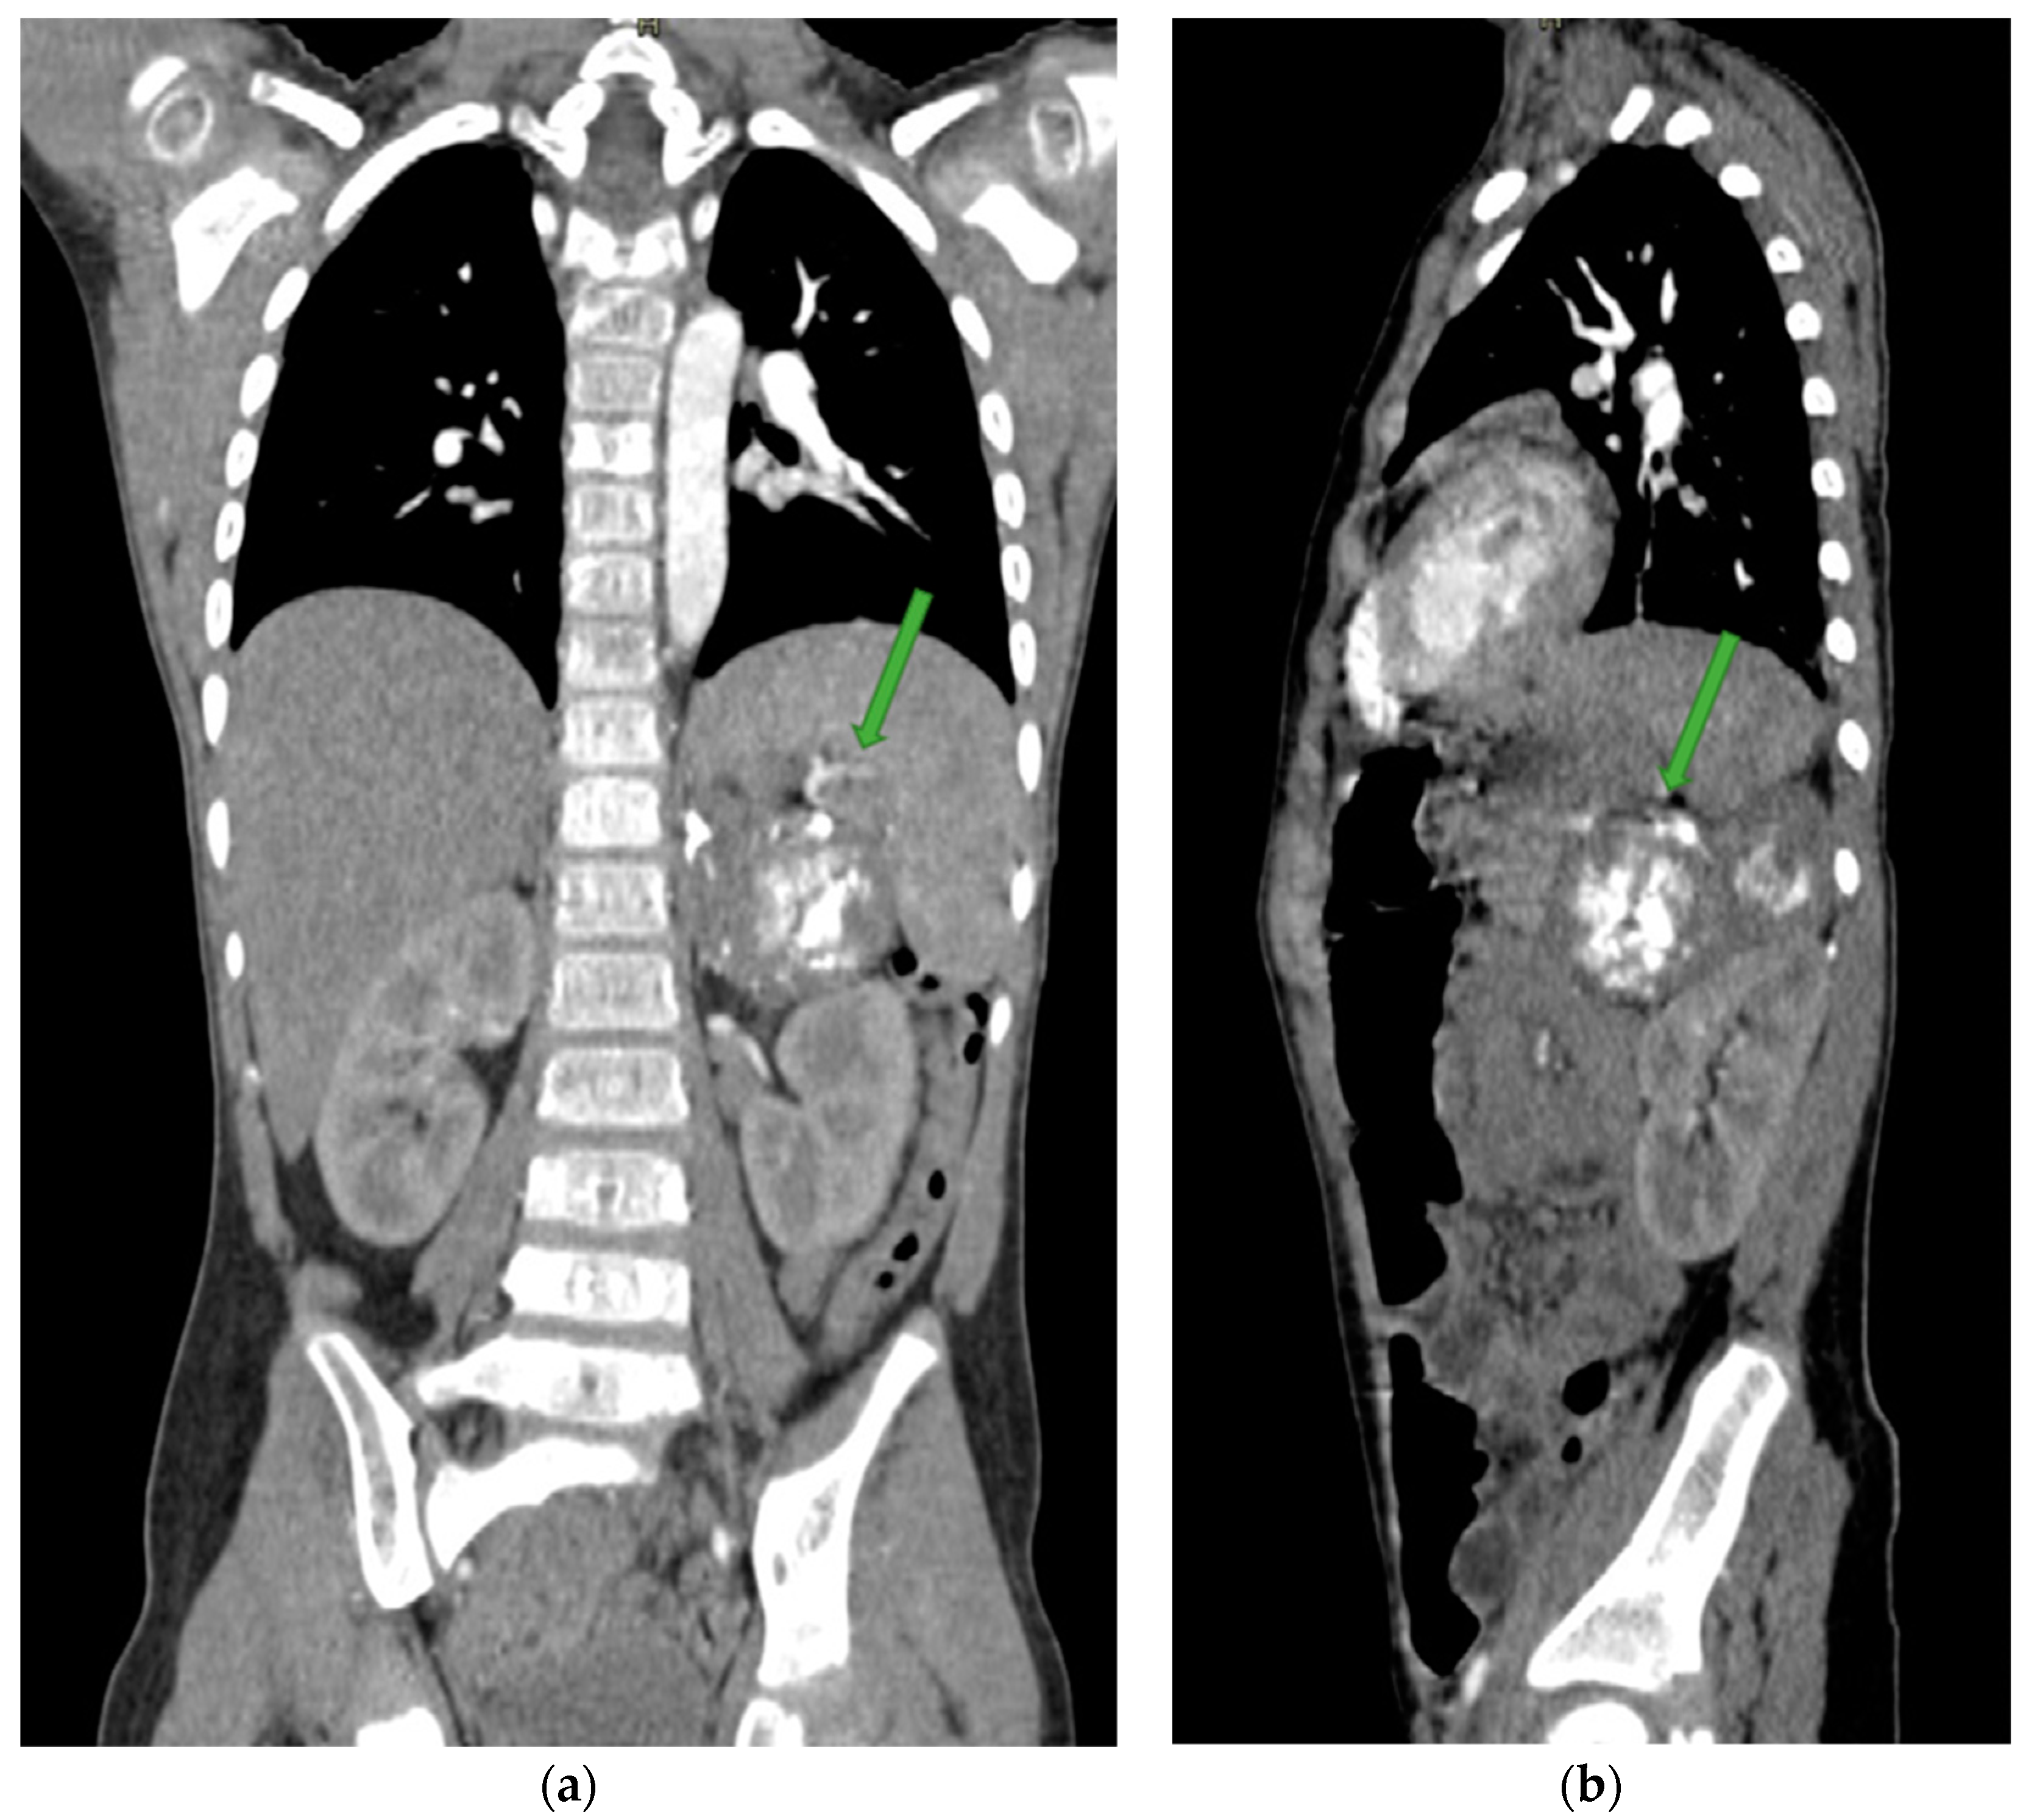

4. Case Presentation